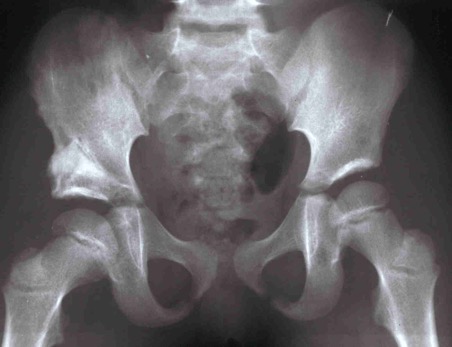

Lussazione dell'anca destra In questo articolo affrontiamo il caso di una piccola paziente affetta la lussazione vera dell’anca dx.

Posta in trazione allo zenit il femore scendeva gradualmente verso l’acetabolo.

Una volta raggiunta l’altezza dell’acetabolo, la paziente veniva operata (Istituto Rizzoli) e ridotta . La paziente veniva ingessata in apparecchio femoropodalico

E successivamente mantenuta in divaricatore di Putti x diversi mesi. Come si può osservare dalla radiografia la testa del femore dx non solo è di ridotte dimensioni ma ha subito una crisi vascolare, come si vede dalla parte mancante. Questo fenomenoo denominato osteocondrite post-riduttiva è dovuto a una crisi vascolare dell’irrorazione della testa femorale